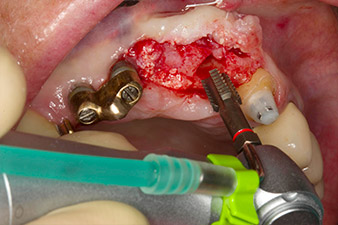

Une fois la cicatrisation primaire obtenue, les tissus mous ont été formés à l'aide du bridge doublé à la base. Deux mois plus tard, la zone a été exposée au moyen d'une incision de la crête alvéolaire légèrement orientée côté palatin (Fig 2). Les dimensions de l'os alvéolaire se sont avérées suffisantes en position 22. Les Figures 2 et 4 illustrent la préparation du lit implantaire, le taraudage et la pose de l'implant à l'aide de l'Implantmed.

Le nouveau moteur d'implantologie a été utilisé avec les contre-angles chirurgicaux de W&H correspondants.

WS-75 L suivant un ratio de 20:1 (programme P5).